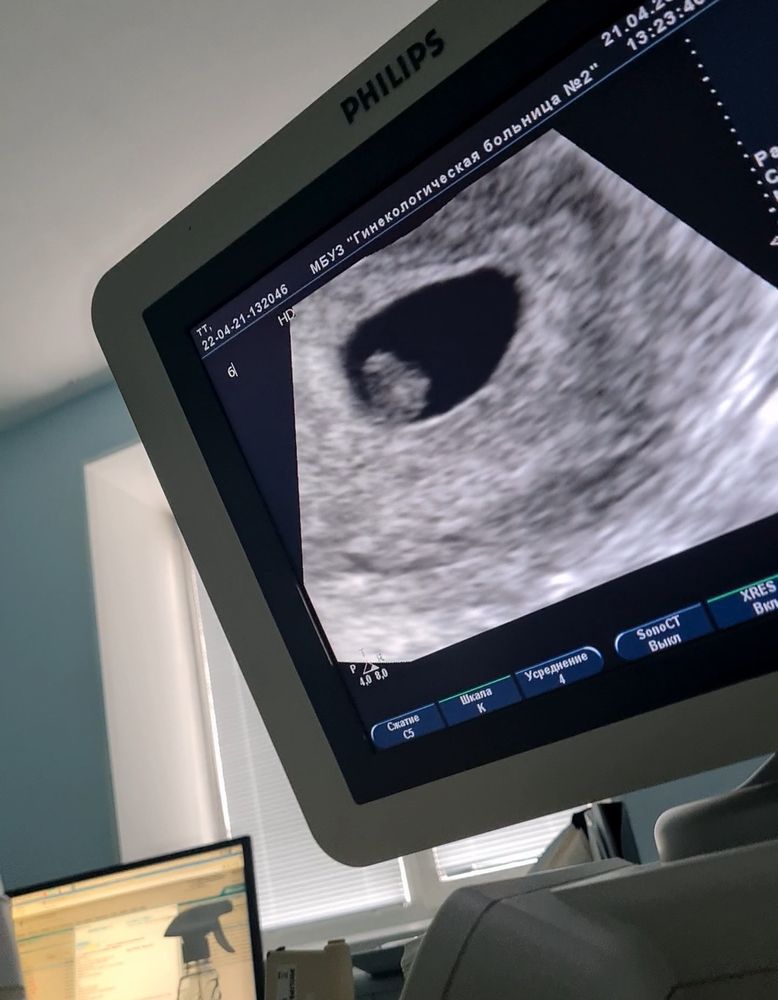

Сегодня отправили на УЗИ, а там и эмбриончик показали и сердцебиение дали послушать, я так была счастлива, что даже всплакнула от радости. Ведь все эти дни в больнице для меня были очень и очень стрессовыми. Сначала исключили внематочную беременность, потом сохранялись, и теперь слава богу мы видим что беременность ПРОГРЕССИРУЕТ🥰💥

Срок акушерский и по УЗИ 6-7 недель, никаких отслоек, никакого тонуса, придатки в норме. Всё (Тьфу-тьфу-тьфу) хорошо.

Даже разрешили сфотать и чуть снять видео...

Делюсь👇🏼👇🏼👇🏼

Наш малышик всего 7 мм, а ЧСС 120 ударов в минуту😍